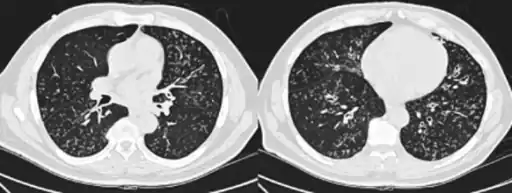

High-resolution computed tomography scan of the thorax -

High resolution computed tomography (HRCT) images of the lower chest in a 16-year-old boy initially diagnosed with DPB (left), and 8 weeks later (right) after a 6-week course of treatment with erythromycin. The bilateral bronchiectasis and prominent centri-lobular nodules with a "tree-in-bud" pattern shows noticeable improvement.